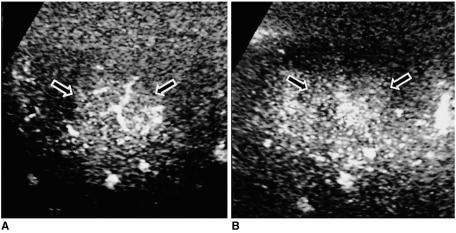

To determine the findings of various focal hepatic lesions at contrast-enhanced gray-scale ultrasound (US) using a coded harmonic angio (CHA) technique and emphasizing lesion characterization.

The study involved 95 patients with 105 focal hepatic lesions, namely 51 hepatocellular carcinomas (HCCs), 22 metastases, 22 hemangiomas, four cases of focal nodular hyperplasia (FNH), and six nontumorous nodules. After the injection of a microbubble contrast agent (SH U 508A), gray-scale harmonic US studies using a CHA technique were performed with a combination of continuous scanning to assess the intratumoral vasculature (vascular imaging) and interval-delay scanning to determine the sequential enhancement pattern (acoustic emission imaging). Each imaging pattern was categorized and analyzed.

At vascular imaging, 69% of HCCs (35/51) showed irregular branching vessels, while in 91% of metastases (20/22) a peripherally stippled pattern was observed. Intratumoral vessels were absent in 95% of hemangiomas (21/22) and all nontumorous lesions (6/6), while in 75% of FNHs (3/4) a spoke-wheel pattern was evident. At acoustic emission imaging, 71% of HCCs (36/51) showed heterogeneous enhancement and 86% (19/22) of metastases showed rim- or flame-like peripheral enhancement during the early phase, with washout occurring in all HCCs and metastases (100%, 73/73) during the late phase. In hemangiomas, enhancement was either peripheral and nodular (19/22, 86%) or persistent and homogeneous (3/22, 14%), and 75% of FNHs (3/4) became isoechoic during the late phase.

At contrast-enhanced gray-scale US using a CHA technique, a period of continuous scanning depicted the intratumoral vasculature, and interval-delay scanning demonstrated the sequential enhancement pattern. The characteristic findings of various focal hepatic lesions were thus determined.